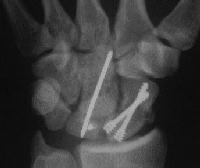

Clinical Example: Scaphoid fixation with more than one Herbert screw

A few years ago, I started putting in two Herbert screws for scaphoid fractures, with the thought that it would provide more rigid fixation. I think that it is helpful in some, but not all cases. Here are some of my results with a few variations...

Case 3. Another postop, better screw positioning.